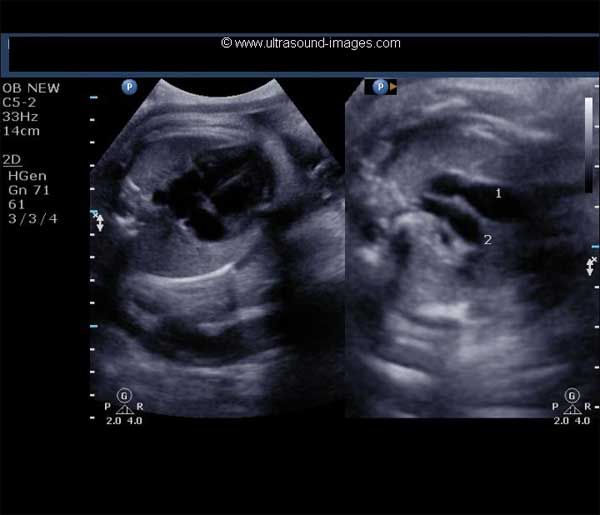

This 53 year-old woman has a uterine lesion and irregular bleeding. Which of the following is the correct diagnosis?